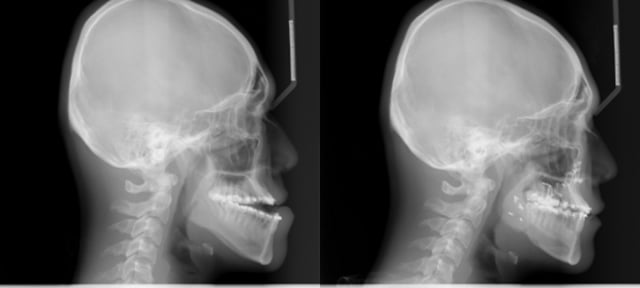

양악수술(orthognathic surgery)은 잘못 위치한 '턱뼈'(gnathologic system)를 '수술'(surgery)을 통해 '고쳐준다'(ortho=correct)는 의미로 턱뼈와 치아의 위치를 정상적인 위치로 교정하는 수술이다. 즉 성형외과병원이 아닌 치과병원에서 구강악안면외과 전문의들이 치료를 목적으로 하는 게 양악수술이다.

입을 다물려고 해도 턱뼈의 구조적 문제로 윗니와 아랫니가 맞물리지 않는 '부정교합', 한쪽 턱뼈가 더 많이 자라나 얼굴이 심하게 일그러지는 '안면비대칭', 앞니가 서로 맞지 않아 음식물을 제대로 못 씹고 발음이 부정확해 일상생활이 어려운 '주걱턱'(하악전돌증) 등이 양악수술 대상이다.

구강악안면외과 전문의들은 치료 목적의 양악수술이 필요하다면 뼈의 성장이 어느 정도 멈추고 회복력은 빠른 17~18세가 가장 적정한 시기라고 밝혔다. 박 교수는 "양악수술의 필요 여부는 치과 교정과에서 1차 판단을 한다"며 "턱뼈가 한쪽 또는 양쪽으로 지나치게 많이 자란 경우 교정으로 치료가 안되기 때문에 수술이 필요하다"고 말했다.

약 2시간 진행된 인터뷰에서 황 교수는 양악수술을 집도하기 위해선 치의학지식이 필수라고 수차례 강조했다. 수술 전 환자의 턱뼈와 관절, 디스크 상태를 점검해 최적의 솔루션을 설계하고 수술 중 변화에 민첩하게 대응하기 위해선 해당 지식의 종합적 이해가 선행돼야 한다는 설명이다.